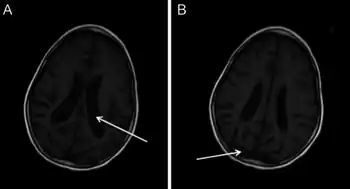

| Diagnostic method | MRI, Genetic testing[3][4] |

- MRI